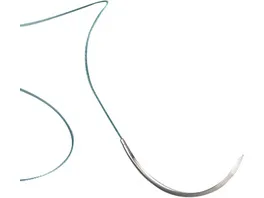

TERVALON braided DS 15, 1,5 EP - 4/0 USP, 1 x 45 cm, 24 ks

CHIRANA T.Injecta

Skladem

1620 CZK

s DPH

€66

67.48 Kč/ks

Balení: 24 ks